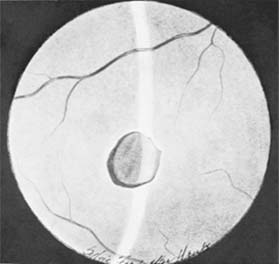

Figure 19-4

Figure 19-4: Choroidal ruptures. (Photo by Diane Beeston.)